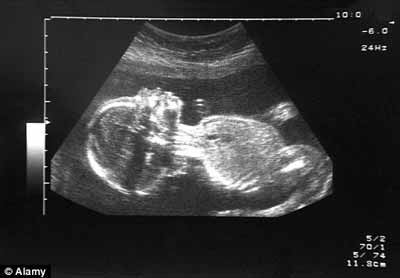

Hiện thai phụ chỉ làm các xét nghiệm chẩn đoán hội chứng Down qua siêu âm, chọc ối, lấy mẫu sinh thiết gai nhau. Nhưng kỹ thuật chọc ối và sinh thiết gay nhau đều làm tăng nguy cơ sẩy thai. Để giảm nguy cơ, các nhà nghiên cứu trên thế giới đã cố gắng dể tìm ra những cách khác để có thể chẩn đoán dị tật thai mà không xâm lấn thai. Ví như các nhà nghiên cứu ở bệnh viện Great Ormond Street đã nghiên cứu thành công kỹ thuật xét nghiệm máu thai phụ ở tuần 12 để phát hiện bệnh beta-thalassaemia, một rối loạn máu đe dọa tính mạng.